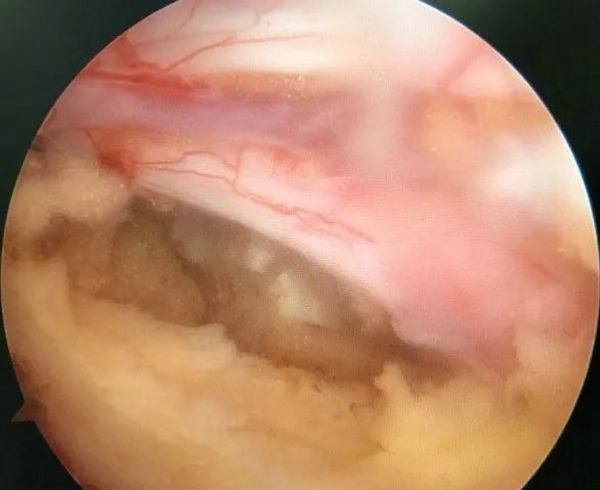

切除后黄韧带和椎间盘髓核组织

患者接受手术治疗,术中仅通过两个长约0.5cm及1cm的手术切口,置入脊柱内镜及操作器械,逐步扩大“狭窄的椎管”并顺利摘除“脱出的椎间盘组织”,解除神经受压情况。